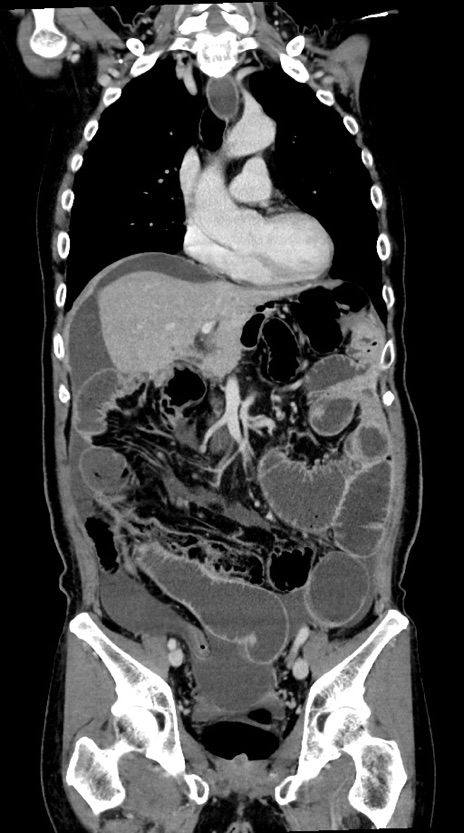

症例28(冠状断像)

【症例】60歳代男性

【主訴】嘔吐

【現病歴】胃癌にて胃全摘後。食思不振が悪化し、夜中に嘔吐することがある。

【既往歴】胃癌、胃全摘、脾摘、胆摘後

【データ】WBC 5900、CRP 10.56